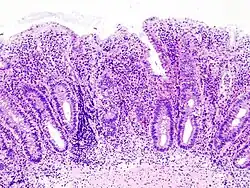

- badania endoskopowe jelita grubego – rektoskopia, kolonoskopia, z pobraniem wycinków do badań histopatologicznych;

Wrzodziejące zapalenie jelita grubego (łac. colitis ulcerosa, CU), zaliczane do grupy nieswoistych zapaleń jelit, jest przewlekłym procesem zapalnym błony śluzowej odbytu lub jelita grubego o nieustalonej dotychczas etiologii.

Choroba charakteryzuje się występowaniem zaostrzeń i okresów remisji o różnym okresie trwania. Najczęściej obejmuje końcową (lewą) część jelita grubego – odbytnicę (która zajęta jest w 95% przypadków), esicę, okrężnicę zstępującą, zagięcie śledzionowe. Rzadziej zajmuje całe jelito grube, aż do zastawki krętniczo-kątniczej. Nigdy nie dotyka bezpośrednio jelita cienkiego. Jedynym objawem może być tzw. backwash ileitis, który występuje w momencie zajęcia jelita grubego na całej długości (pancolitis) wraz z zastawką krętniczo-kątniczą, która staje się niewydolna i przepuszcza mediatory procesu zapalnego w kierunku końcowych odcinków jelita krętego. W odróżnieniu od choroby Leśniowskiego-Crohna we wrzodziejącym zapaleniu jelita grubego istnieje znacznie mniejsza tendencja do powstawania przetok okołoodbytniczych, ropni i perforacji jelit. Występuje natomiast większe prawdopodobieństwo powstania raka jelita grubego. Skłania to do wykonywania regularnych kolonoskopii diagnostycznych u osób długotrwale chorujących na wrzodziejące zapalenie jelita grubego. Ze względu na zajęcie przez chorobę dystalnej części odbytnicy dużą wartość diagnostyczną ma również wykonanie rektoskopii.